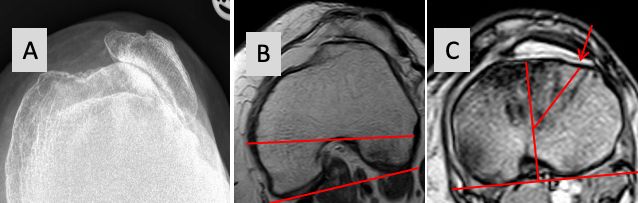

Severe proximal tibia rotational deformities > 30° are very rare and need a rotational profile of the whole leg to analyse the maltorsion syndrome (Fig 24 A and B).

Whereas rotational deformities at the femur are mostly corrected in the hip joint severe external torsional deformities at the tibia might need proximal internal derotation osteotomy combined with TKA. This remains a very complex surgery including TT osteotomy, bony derotation and use of stem and external fixation [59] (Fig 26 A to C).

In our experience we use this technique in young patients with native knees only, but it was never necessary for TKA patients. In these severe tibial axial deformities, a combination of PS or CCK constraint, TT osteotomy, lateral retinaculum release and proximal realignment can correct the deformity. Combined with the correction of the distal femur axial plane deformity inside the joint this will produce proper patella tracking even in patients with permanent patella dislocation before surgery (Fig 14 and 27).